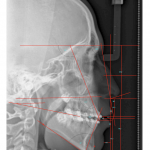

- Steiner